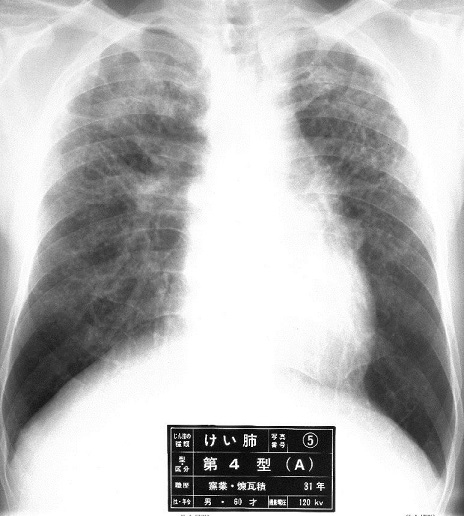

遊離圭酸によるじん肺である珪肺のレントゲン像は、上肺野優位の粒状影、大陰影が特徴的である。

一方石綿肺は下肺野優位の不整型陰影が出現する。

下肺野優位の不整型陰影を「じん肺標準エックス線写真」と比較して判定することになる。

0型(-/1、0/0、0/1):PR0

1型(1/0、1/1、1/2):PR1

2型(2/1、2/2、2/3):PR2

3型(3/2、3/3、3/+):PR3

の12通りの診断となり、Ⅰ刑以上の所見がある場合、石綿肺と診断することになる。